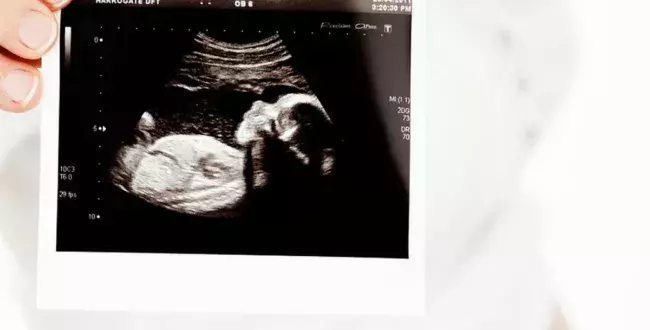

Od wczoraj wszystkie kobiety w ciąży mają prawo do badań prenatalnych. Badania te pozwalają wcześnie wykryć wady płodu oraz rozpocząć ich diagnostykę we wczesnym okresie ciąży oraz – w miarę możliwości – rozpocząć leczenie jeszcze w okresie płodowym. Dotychczas badania prenatalne mogły wykonać kobiety, które skończyły 35 lat. Te ograniczenia wiekowe zostały już zniesione. Dzięki temu zwiększył się dostęp do badań prenatalnych dla wszystkich kobiet. Według Agencji Oceny Technologii Medycznych i Taryfikacji z programu może skorzystać ponad 210 tys. kobiet.

Badania prenatalne pozwalają wcześnie wykryć wady płodu, zdiagnozować i rozpocząć leczenie już podczas ciąży – jeżeli jest taka możliwość.